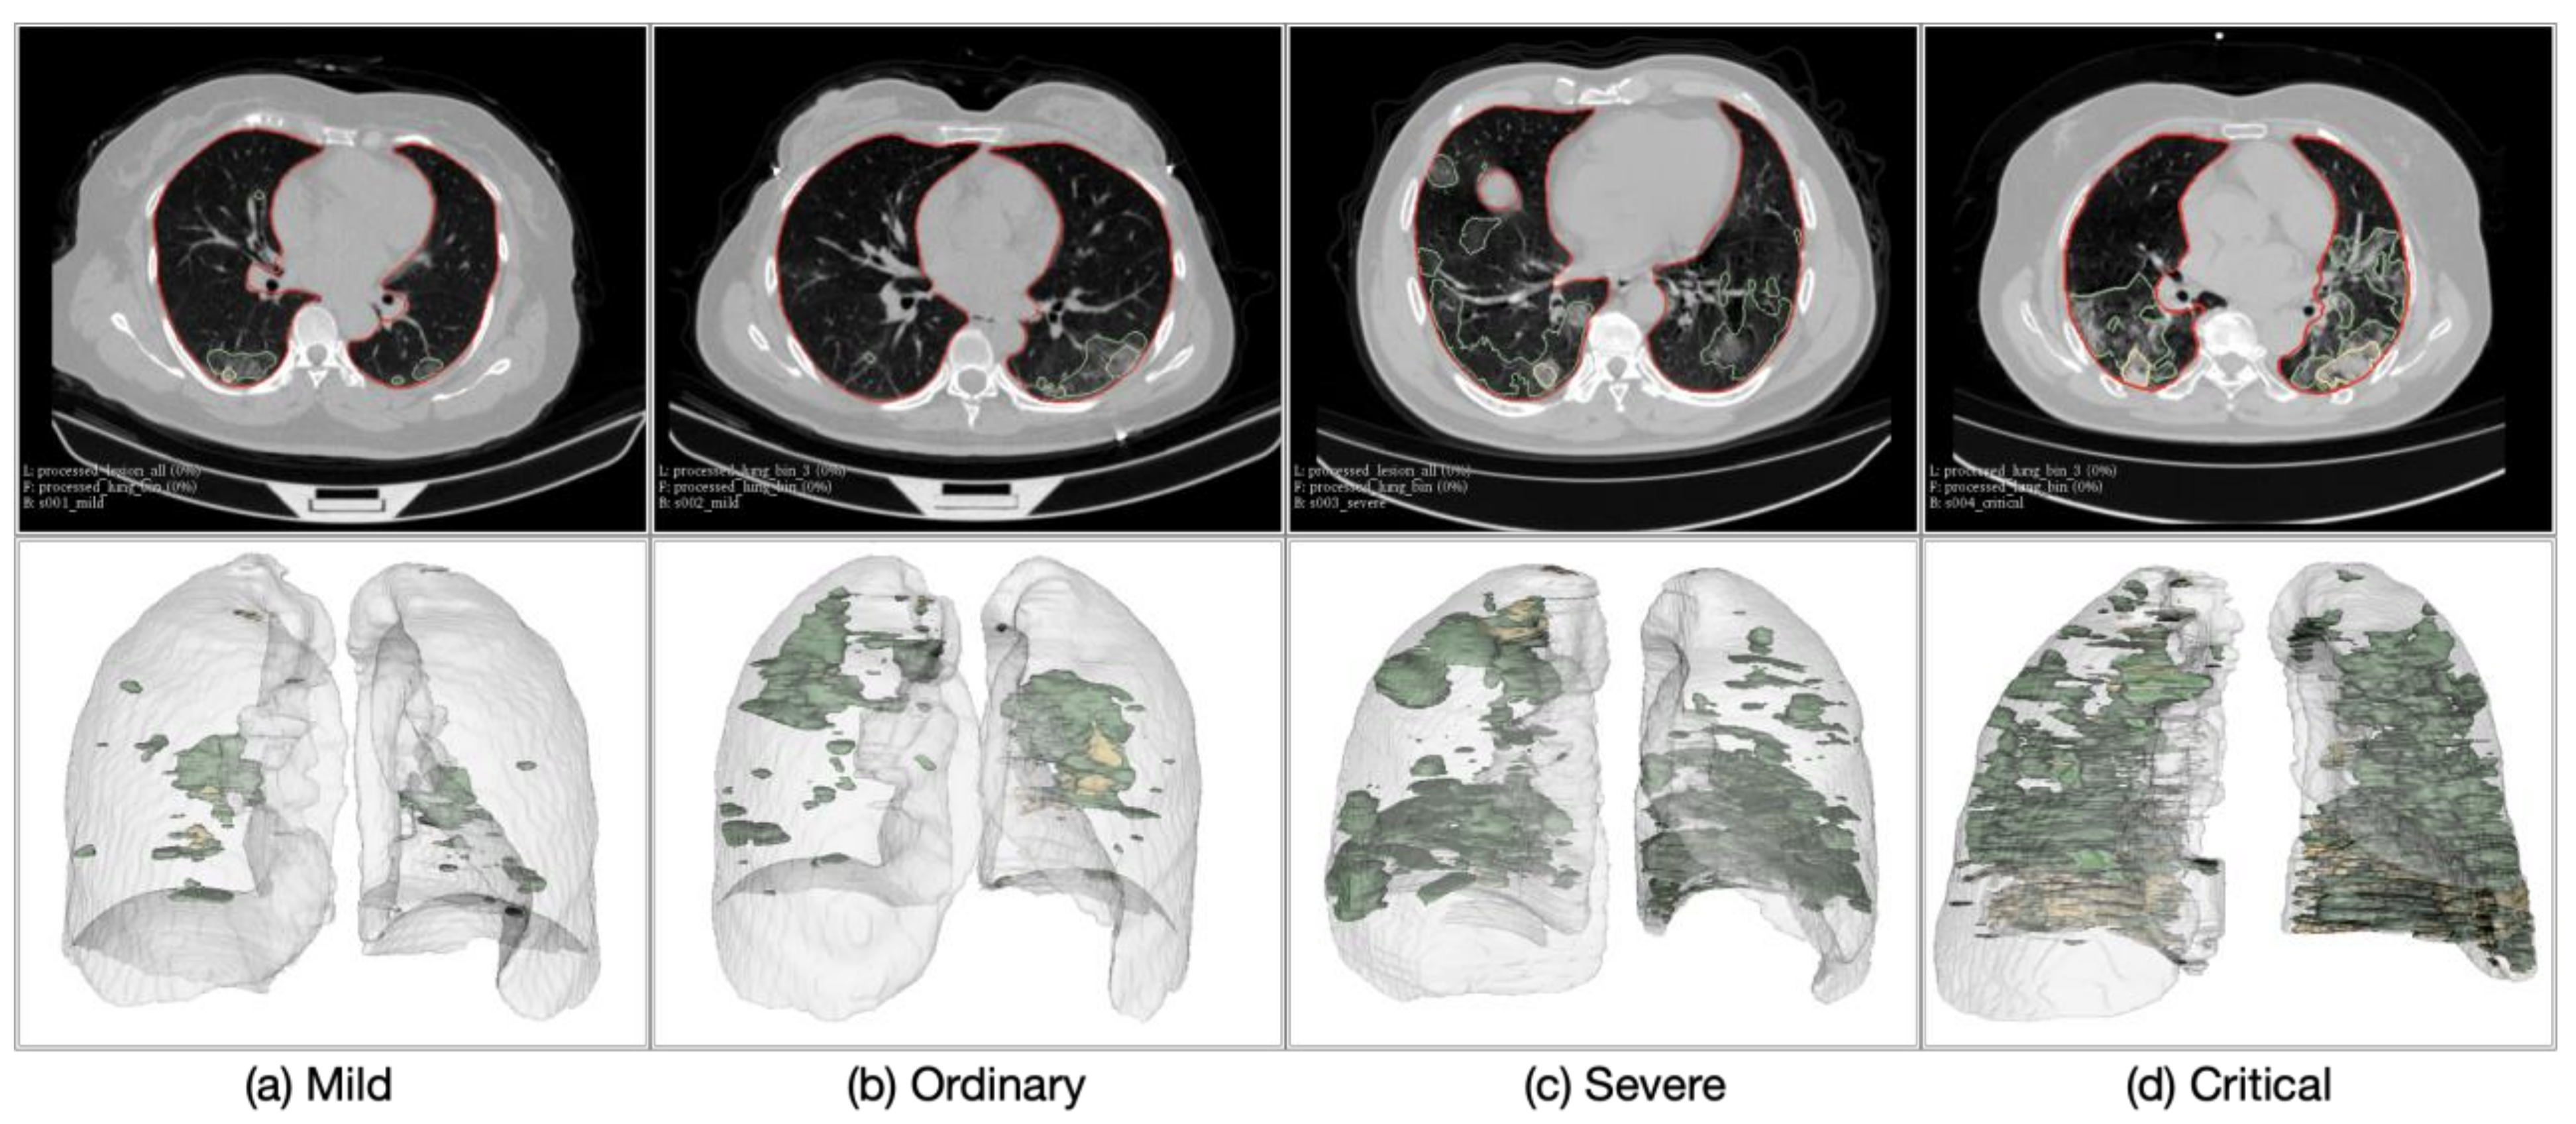

4.2. Severity Assessment